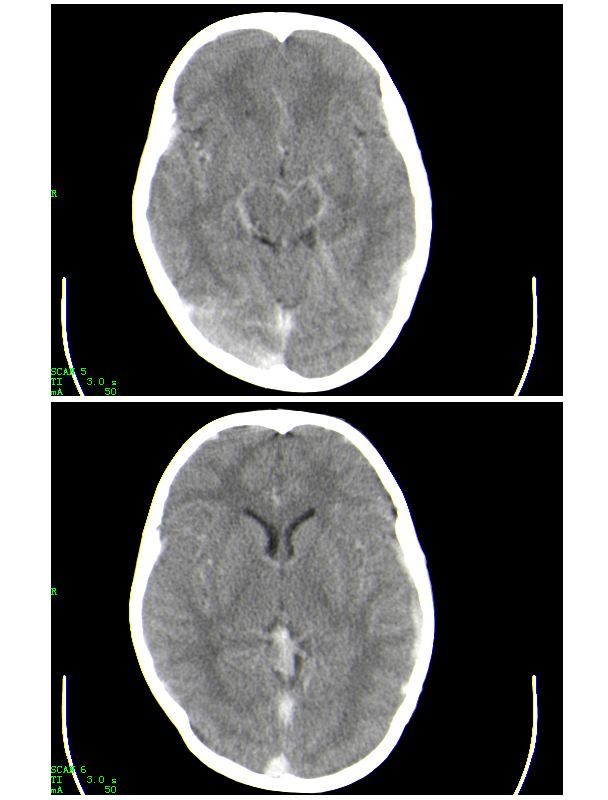

男,13岁,头部外伤后头痛、呕吐三小时就诊,查体,见小孩精神状态尚可,面部,嘴唇青紫明显,后作心脏彩超证实为“发四”,有复查片,大家先看看首诊片,考虑什么

初步考虑硬膜下、蛛网膜下积液

还是考虑蛛血吧~~~~

考虑蛛网膜下腔出血

1.有点像强化片背景,考虑为高血红蛋白症;2.脑沟、上矢状窦、小脑幕、大脑脚周围高密度影考虑蛛网膜下腔出血。

考虑1.蛛网膜下腔出血,2.左顶部硬膜下血肿,3.弥漫性轴索损伤

1.有点像强化片背景,考虑为高血红蛋白症;2.脑沟、上矢状窦、小脑幕、大脑脚周围高密度影考虑蛛网膜下腔出血

考虑是高血红蛋白血症,因为从ct上看,密度增高部分都是和颅内血管,静脉窦的走行方向一致的,至于有没有sah,还要靠复查的片子来确定。

感谢大家的关注,本例我们最后诊断为高血红蛋白症所致的脑血管改变,患者血红蛋白258g/l

下面是第二天的复查和受伤后第五天的复查,左侧硬膜下血肿有所吸收,脑内条状高密度无改变